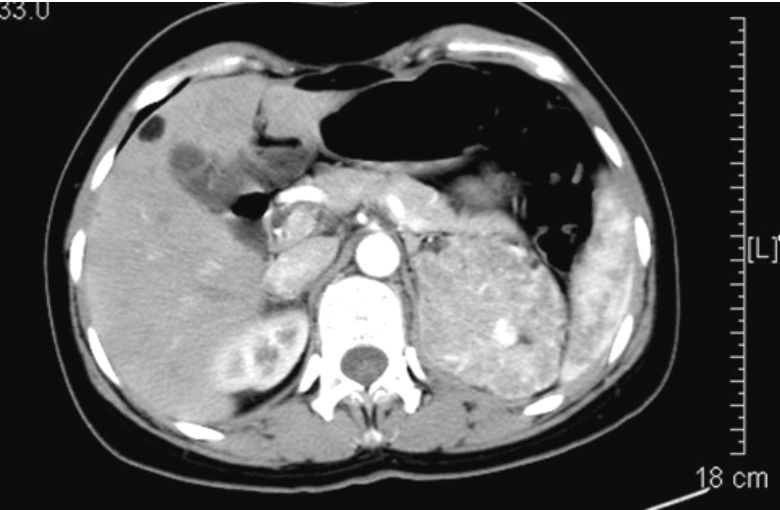

臨床資料?患者女性,27歲,自由職業者,已婚,未育。因突發胸悶伴胸痛4 d入院。查體:體溫36.8 ℃,脈搏96次/min,呼吸18次/min,血壓101/69 mm Hg(1 mm Hg=0.133 kPa),血氧飽和度(SpO2 )89%(自然狀態)。右上肺呼吸音消失,左肺呼吸音清,兩肺未聞及干濕性啰音。心腹四肢未見異常。胸片示右側氣胸(肺組織壓縮約30%),右側胸腔少量積液(圖 1)。心電圖、血常規及肝腎功能正常。動脈血氣分析示PaO2 58 mm Hg,PaCO2 35 mm Hg,SaO2 94%。胸部CT示右側少量氣胸,雙肺散在大小不等薄壁囊泡,左上肺囊泡有融合,兩側少量胸腔積液,左腎占位性病變,建議進一步查腎臟 CT(圖 2)。抽取少量胸水示乳糜性胸腔積液。生化檢查示甘油三酯升高為49.5 mmol/L。雙腎增強CT示肝內多發脂類占位,左腎占位性病變考慮惡性(圖 3)。雙腎MRI示左腎上極占位性病變,所顯示肝臟多發占位性病變,考慮錯構瘤(圖 4)。患者轉院行腹腔鏡下左腎根治性切除術,術后病理學檢查:大體所示左腎上極可見1個9 cm×7 cm×6 cm的腫物,切面灰白質脆;組化13-3914:CK(-),Vim(+),S-100(+),Des(-/+),Ki-67(1%),HMB45(散在+),SMA(+)(圖 5)。家屬拒絕行經支氣管鏡肺活檢(TBLB)及胸腔鏡肺活檢。根據患者的年齡、性別、胸部CT、腎臟增強CT及腎臟術后病理、胸水檢查,該患者診斷:肺淋巴管肌瘤病伴左腎血管平滑肌脂肪瘤。患者放棄治療出院。